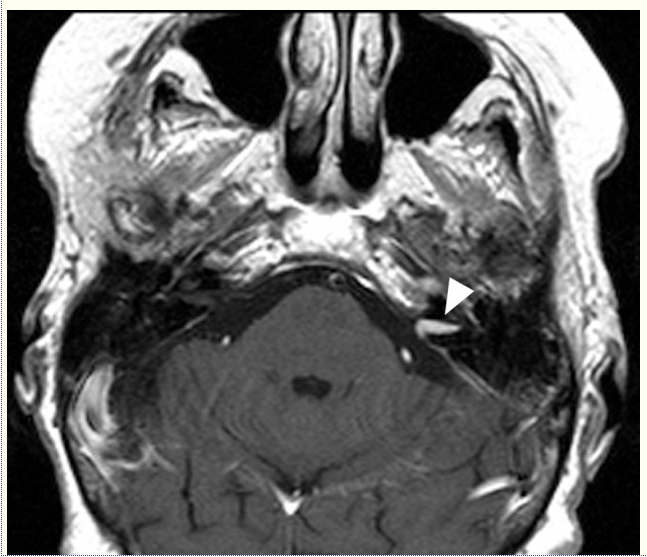

A variety of neoplasms can cause SSNHL, particularly vestibular schwannomas (acoustic neuromas). The incidence of vestibular schwannoma in series of patients with SSNHL ranges from none to 48%, although most studies find at least one or two within their groups of patients (Byl, 1984; Cadoni et al., 2005; Chau et al., 2010; Fitzgerald & Mark, 1998; Heman-Ackah et al., 2010; Nosrati-Zarenoe, Hansson, & Hultcrantz, 2010; Tucci, Farmer, Kitch, & Witsell, 2002; Xenellis et al., 2006). One review estimated the incidence of all neoplastic causes of SSNHL at 2.3%. This figure includes more rare metastatic and benign tumors as well as vestibular schwannomas (Chau et al., 2010). Return of hearing does not indicate that neoplasms are absent as SSNHL due to these causes can potentially recover spontaneously or after treatment with systemic steroids (Berg, Cohen, Hammerschlag, & Waltzman, 1986; Nageris & Popovtzer, 2003). Thus evaluation of patients with SSNHL for neoplasms cannot be omitted in patients with complete hearing recovery (Figure 2).

MRI of patient with SSNHL. This patient’s moderate flat SSNHL resolved completely following treatment with 1mg/kg prednisone and oral antiherpetic medications for 10 days followed by a short prednisone taper. Note small left intracanalicular enhancing mass consistent with vestibular schwannoma (arrowhead). MRI, magnetic resonance image; SSNHL, sudden sensorineural hearing loss.